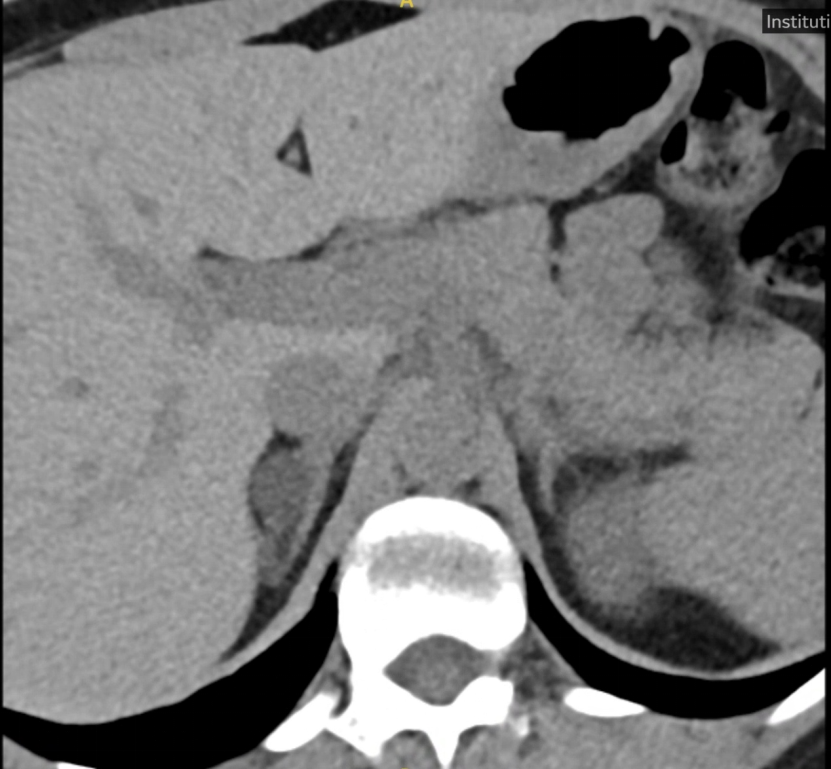

患者肾上腺CT影像示右侧腺瘤